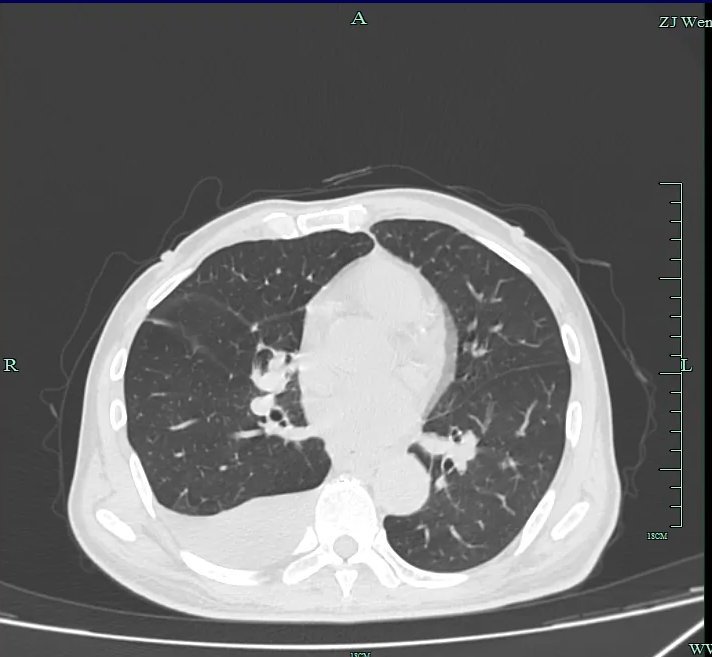

接下来进入「GPS 定位」环节。DSA 设备化身「淋巴管导航仪」,通过 360°旋转拍摄,医生能清晰看到造影剂在淋巴管内的流动轨迹。当发现某处管径突然增宽或造影剂外溢时,就找到了导致乳糜胸的「决堤口」。

经过 2 小时的手术,朱大伯的引流量显著减少,术后 6 小时即可下床活动,最终拔除所有胸管自由呼吸,经复查显示胸腔积液明显改善。